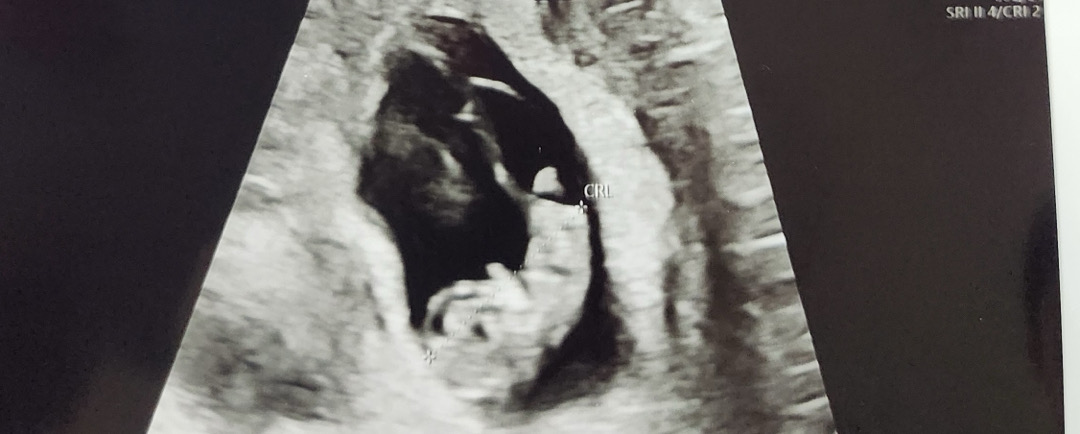

저는 이때뿐이라 너무 간직하고싶어서 곰돌이 모양으로 딱! 찍어달라고 말씀드렸더니 딱! 찍어주셨어요 ㅎㅎㅎㅎㅎㅎ

젤리곰 잘 만들어진건가요..?

오늘 9주 4일차인데 사람형태가 되어 있어서 넘 신기했어요 ㅎㅎ 근데 다른 분들 촘파 사진보니 앞모습? 같은데 전 조금 다른 것 같더라구요 아기의 위치에 따라 앞,옆모습 다르게 보이는걸까요~?

우아앗 완전 하리보 그자체네요!!! 팔다리 너무 귀엽자나요ㅠㅠㅠ